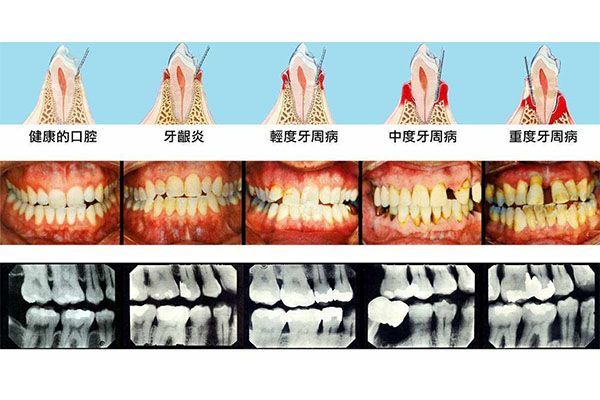

你好!儿童时期牙齿出现黑渍,首先应排除龋齿的可能。龋齿俗称虫牙、蛀牙,是细菌性疾病,可以继发牙髓炎和根尖周炎。如不及时治疗,病变继续发展,形成龋洞,终至牙冠被完全破坏。细菌感染与蔗糖及碳水化合物饮食过多是主要的致病原因。平时应戒掉糖类及碳水化合物过多的食品,仔细刷牙,勤漱口。如果不是龋齿,考虑是牙渍,应进一步加强口腔卫生护理。

饮食习惯对牙齿颜色有直接阻碍。经常摄入含色素高的食物如咖啡、茶、红酒等,容易使得牙齿着色。如果不经常进行深层清洁和美白,色素沉着会逐渐加重,最终使得牙齿永久性变色。牙齿美白有助于减少口腔疾病的发生。牙齿表面的色素沉着可能隐藏细菌和食物残渣,在这方面都是造成龋齿和牙周病的因素。通过美白去除在这方面色素,可以减少口腔疾病的可能性。猜你喜欢:去除牙齿上黑色污垢